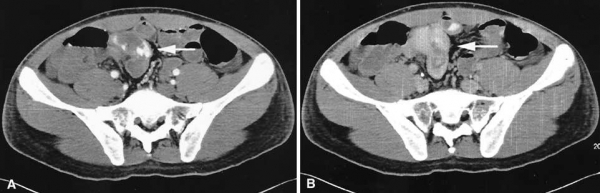

Mạch máu nuôi túi thừa Meckel là mạch máu còn lại của mạch máu rốn ruột, đây là dấu hiệu để chẩn đoán túi thừa Meckel trên DSA. Ở một vài bệnh nhân mạch máu nuôi túi thừa Meckel có thể đến từ các nhánh của động mạch hồi đại tràng. Động mạch rốn ruột thường bắt nguồn từ đoạn xa nhánh hồi tràng của động mạch treo tràng trên.

Hình 8: Hình ảnh túi thừa Meckel ở bệnh nhân nữ 22 tuổi bị đau bụng và thiếu máu mạn. A, Hình DSA thấy động mạch rốn ruột bắt nguồn từ đoạn xa nhánh hồi tràng của động mạch treo tràng trên (mũi tên). B, thì động mạch trễ cho thấy đám mạch máu có dạng ống ở bờ của túi thừa (mũi tên). C, Sau phẫu thuật : túi thừa Meckel xuất huyết. (Angela D. Levy, Christine M. Hobbs (2004). Meckel Diverticulum: Radiologic Features with Pathologic Correlation. RadioGraphics; 24:577)